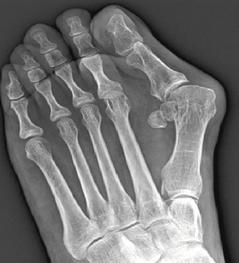

大腳趾外翻,X光片下可見第一蹠骨的角度明顯向外傾斜。

如何判定大腳趾外翻?基本上,除了X光檢查,觀察大腳趾及第一蹠骨角度不超過15度,可判斷大腳趾是否變形。此外,若腳底長繭,或大腳趾指甲不平,且向外轉,還應注意腳趾受力問題,必要時也要治療。